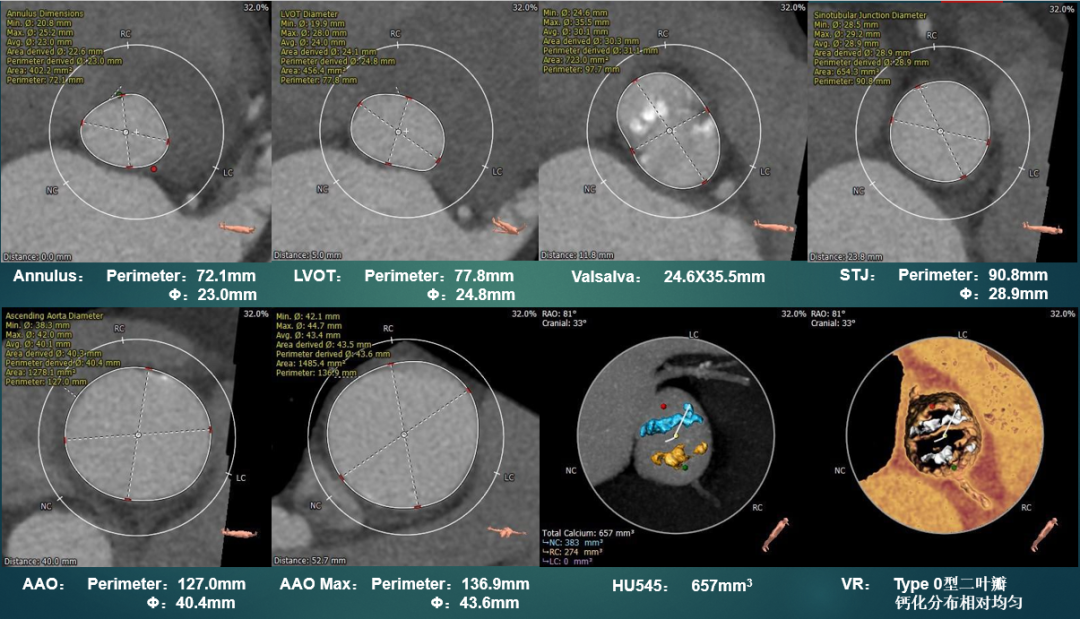

主动脉根部测量

CT特点:Type 0型二叶式主动脉瓣,左右冠不同窦,瓣叶中度钙化伴增厚,钙化分布相对均匀,主要分布于瓣叶边缘及其附着缘,瓦氏窦及窦管交界内径可,升主动脉内径扩张,最大径约43.6mm,左右冠脉开口高度可,无冗长瓣叶;非横位心,心室壁肥厚,心腔偏小,降主动脉及双侧髂总动脉分叉处可见多发钙化斑块。

瓣上测量

瓣上测量:瓣叶中度钙化,钙化分布相对均匀,钙化主要分布在瓣叶边缘及瓣叶附着缘,锚定力量主要来源于瓣上6-10mm。